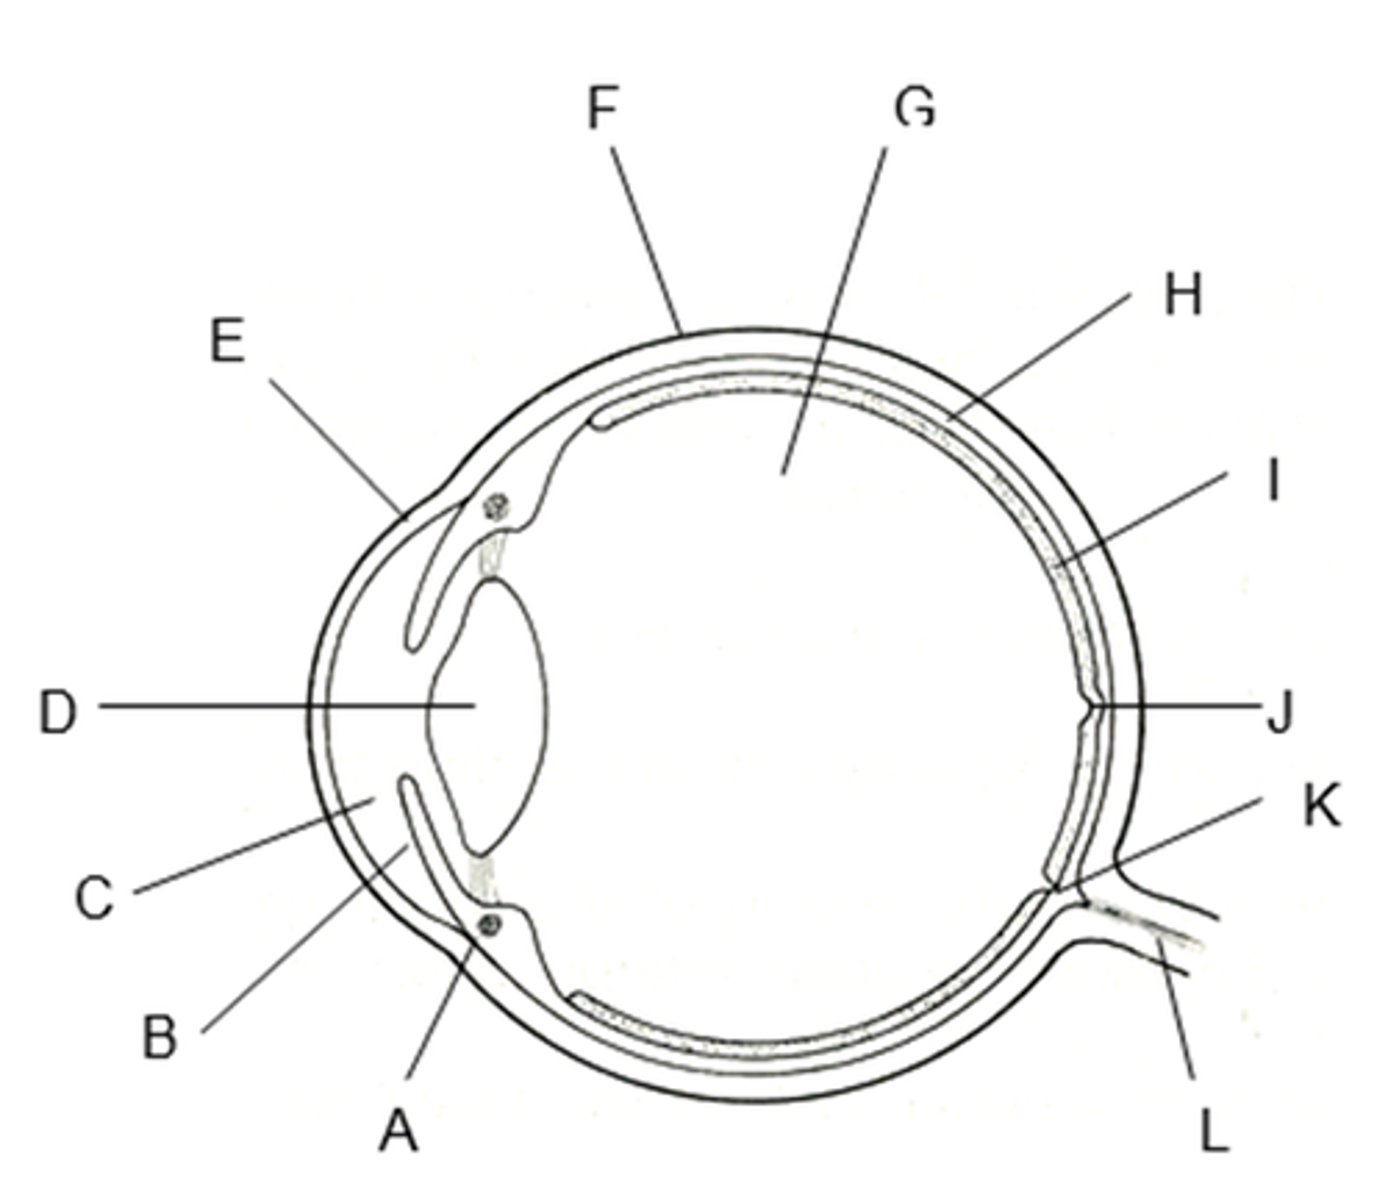

anterior cavity (of eye)

iris

B

optic disk (blind spot)

choroid

L

ciliary body

B

ciliary process

conjunctiva

cornea

D

fovea centralis

suspensory ligaments

C

vitreous humor

lens

H

macula lutea

nasolacrimal duct

lacrimal gland

posterior cavity (of eye)

pupil

F

retina

M

sclera

optic nerve